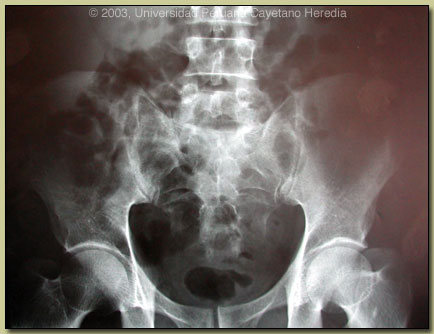

| Diagnosis: Sub-acute brucellosis (due to Brucella melitensis) with multiple concomitant complications. |

| Discussion: Most patients with brucellosis present with systemic febrile disease with no overt complications. This patient is very illustrative as he nicely illustrates multiple complications all during the course of the same illness. While hepatomegaly and mild elevation of liver enzymes are seen in 50-70% of acute cases, clinically evident hepatitis with jaundice is seen in only 3-6%. While a number of other diseases might have been thought of on the initial presentation of this patient (viral hepatitis, typhoid, leptospirosis, TB; there is no malaria in Lima), brucellosis needs to be always considered. Sacro-illitis is the most common articular manifestation in sub-acute brucellosis although it is usually unilateral (80% of the time). Brucellosis should always be a consideration in a febrile patient with fairly new onset of severe back pain with inability to bear weight. Epididymitis occurs in 3-10% of young male patients so it should be thought of along with STDs and viral diseases.